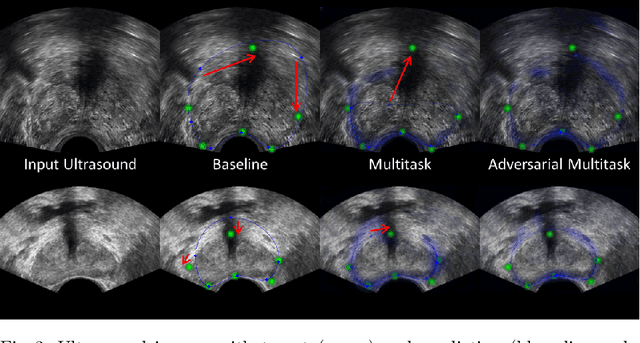

Abstract:Real-time localization of prostate gland in trans-rectal ultrasound images is a key technology that is required to automate the ultrasound guided prostate biopsy procedures. In this paper, we propose a new deep learning based approach which is aimed at localizing several prostate landmarks efficiently and robustly. We propose a multitask learning approach primarily to make the overall algorithm more contextually aware. In this approach, we not only consider the explicit learning of landmark locations, but also build-in a mechanism to learn the contour of the prostate. This multitask learning is further coupled with an adversarial arm to promote the generation of feasible structures. We have trained this network using ~4000 labeled trans-rectal ultrasound images and tested on an independent set of images with ground truth landmark locations. We have achieved an overall Dice score of 92.6% for the adversarially trained multitask approach, which is significantly better than the Dice score of 88.3% obtained by only learning of landmark locations. The overall mean distance error using the adversarial multitask approach has also improved by 20% while reducing the standard deviation of the error compared to learning landmark locations only. In terms of computational complexity both approaches can process the images in real-time using standard computer with a standard CUDA enabled GPU.